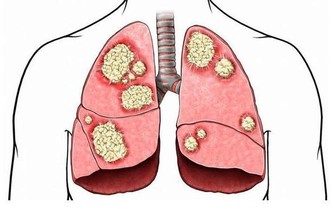

2、維生素D中毒

維生素D在所有維生素中是最容易使人中毒的一種,其中毒症狀和體徵主要有:高鈣血、肌無力、感情淡漠、頭痛、厭食、噁心、嘔吐、骨痛、異位性鈣化、蛋白尿、高血壓和心律失常等。慢性高鈣血可導致全身血管鈣化、腎臟鈣質沉著和迅速出現腎功能衰退。